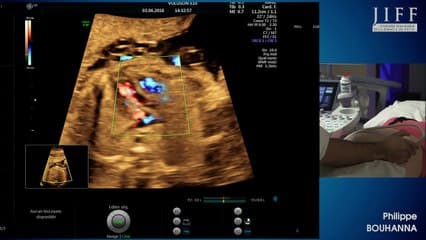

La plus grande ressource vidéo en échographie fœtale de France. Conférences, cours magistraux, démonstrations pratiques et podcasts par les experts du Collège Français d'Échographie Fœtale.

La médiathèque du Collège Français d'Échographie Fœtale (CFEF) constitue l'une des plus importantes collections de ressources vidéo dédiées à l'échographie fœtale en France. Avec plus de 3 261 vidéos, elle couvre l'ensemble des thématiques liées à la pratique échographique prénatale.

Vous y trouverez des conférences présentées lors des congrès nationaux et internationaux, des cours magistraux dispensés par des experts reconnus, des démonstrations pratiques sur des cas cliniques réels, ainsi que des podcasts et tables rondes sur les dernières avancées de la spécialité.